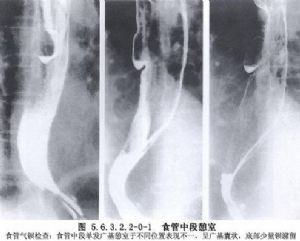

食管中段憩室的诊断主要依靠食管钡餐造影检查和内镜检查。在做钡餐造影检查时,患者取头低脚高位或俯卧位,或取左侧卧位,憩室的位置和轮廓容易显示。必要时做食管CT检查和食管功能测定,以除外其他较严重的疾病。如果出现慢性肺化脓症的症状,则有必要做气管镜检查和肺CT扫描,以明确肺部病变的范围。如怀疑有憩室-支气管瘘,须做支气管碘油造影或气管镜检查;内镜检查有助于发现瘘口。嘱患者口服亚甲蓝或其他染料,若在痰中发现蓝色,即可以确诊(图5.6.3.2.2-0-1~5.6.3.2.2-0-4)。